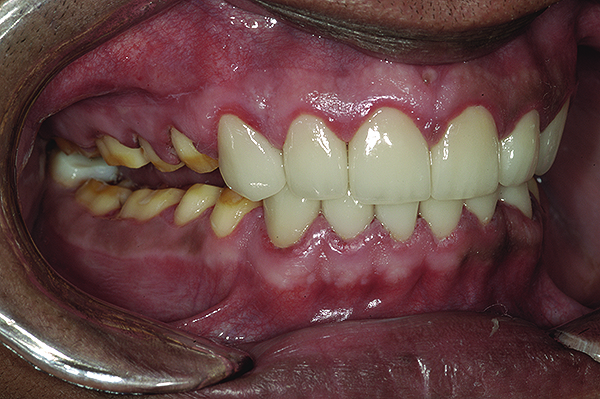

Figure 25. Final restoration with mandible in left lateral excursion.

Figure 25

The final restorations depicted restoration of form, function, and beauty, with good harmony of restoration and the periodontium (Figure 19 through Figure 25). MIP was in harmony with CR, and right and left lateral excursion discluded all posteriors with anterior group function. The postoperative orthopantomogram (OPG) (Figure 26) shows the treatment done while maintaining the vitality of anterior teeth.